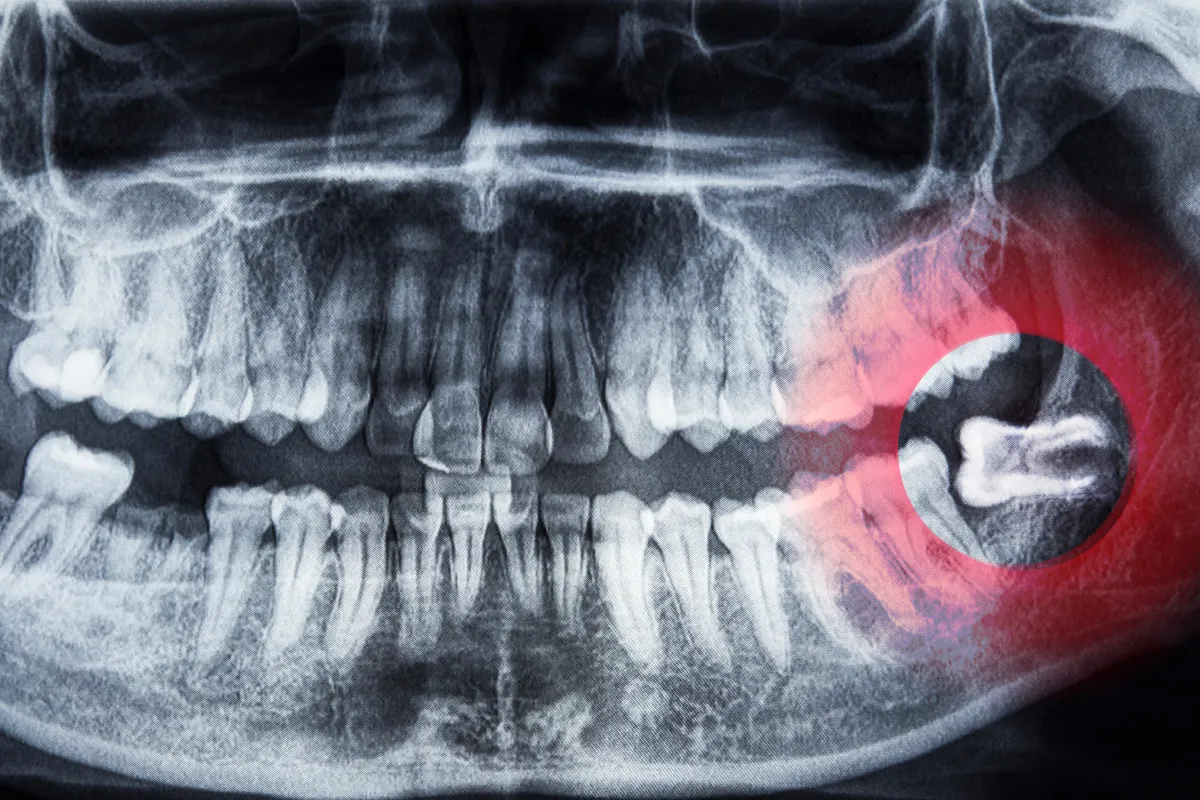

Our dentists, including Dr. Brenda Schobert, Dr. Khalid Aldorri, and Dr. Safa Alathari will examine your teeth and take X-rays to assess the position and condition of your wisdom teeth. -

- They are impacted (stuck beneath the gums)

This may involve cutting the gum tissue or bone if the teeth are impacted. -